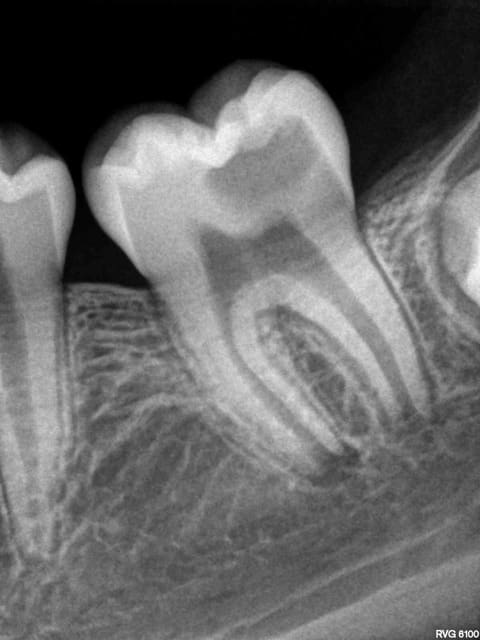

Photo fysbpm - Eugenol

X ray 03 medium zvq18j - Eugenol